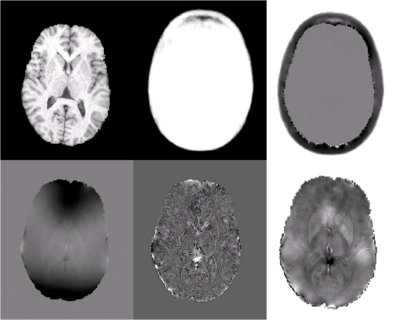

ASM results for a young subject are shown in Fig. 1. Column 1 shows the T1 structural (row 1) and acquired fieldmap (row 2). Application of the Laplacian to the field map (row 2, column 2) removes substantial B0 inhomogeneities that bias the observed field. The susceptibility atlas is shown in row 1, column 2 and estimated external sources are shown in row 1, column 3. The estimated susceptibility map (row2, column 3) shares high frequency structure with the Laplacian of the observed field, while low frequency structure is preserved by enforcing agreement with additional information provided by the atlas-based prior and observed field.

Fig. 1: ASM Results. The first column shows the T1 structural image (row 1) and field map (row 2) with substantial inhomogeneity that was obtained from a young subject. Column 2 shows the susceptibility atlas (row 1), in which voxels take continuous values between [0,1] corresponding to susceptibility values between air and tissue. Taking the Laplacian of the fieldmap successfully eliminates biasfields (row 2, column 2). Estimates of external sources are shown in row 1, column 3. The estimated susceptibility map (row 2, column 3) shares similar high frequency structure with the Laplacian of the observed field while low frequency structure is preserved by enforcing agreement with the atlas and observed field.